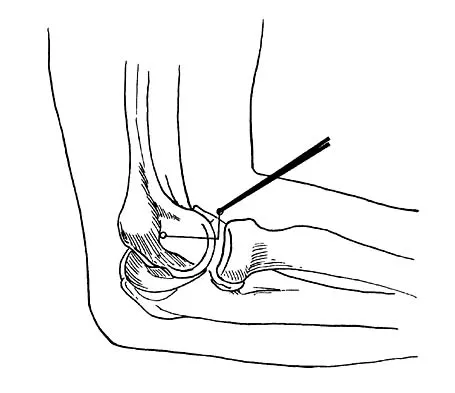

Question 24

The essential lesion responsible for posterolateral rotatory instability of the elbow is disruption of the